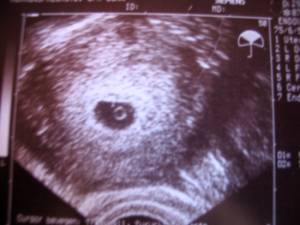

Das Bildchen unten ist noch ohne Herzschlag, kann aber auch an den US-Gerät liegen, denn meine FÄ hat bessere Geräte in der Praxis, als die in der Uni.

Bildchen ist von 5+2